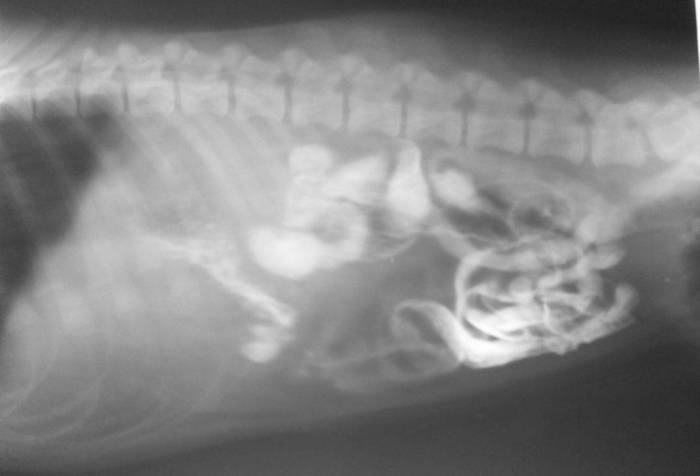

Симптомы и диагностика: Кошки с кишечной непроходимостью могут проявлять такие симптомы, как рвота, отсутствие аппетита, запоры или, наоборот, диарея. Важно отметить, что симптомы могут развиваться быстро, и при подозрении на непроходимость необходимо немедленно обратиться к ветеринару. Диагностика часто включает рентгенографию или ультразвуковое исследование.

Диагностика кишечной непроходимости может осуществляться с помощью различных методов, таких как рентгенография кишечника, ультразвуковое исследование, компьютерная томография и колоноскопия. Кроме того, может быть выполнен анализ кала для выявления бактерий и паразитов.

При подозрении на непроходимость часто назначают рентгенографию с использованием контрастного вещества, такого как сернокислый барий. Эта процедура может помочь выявить инородные тела, однако не все объекты видны на рентгеновских снимках.